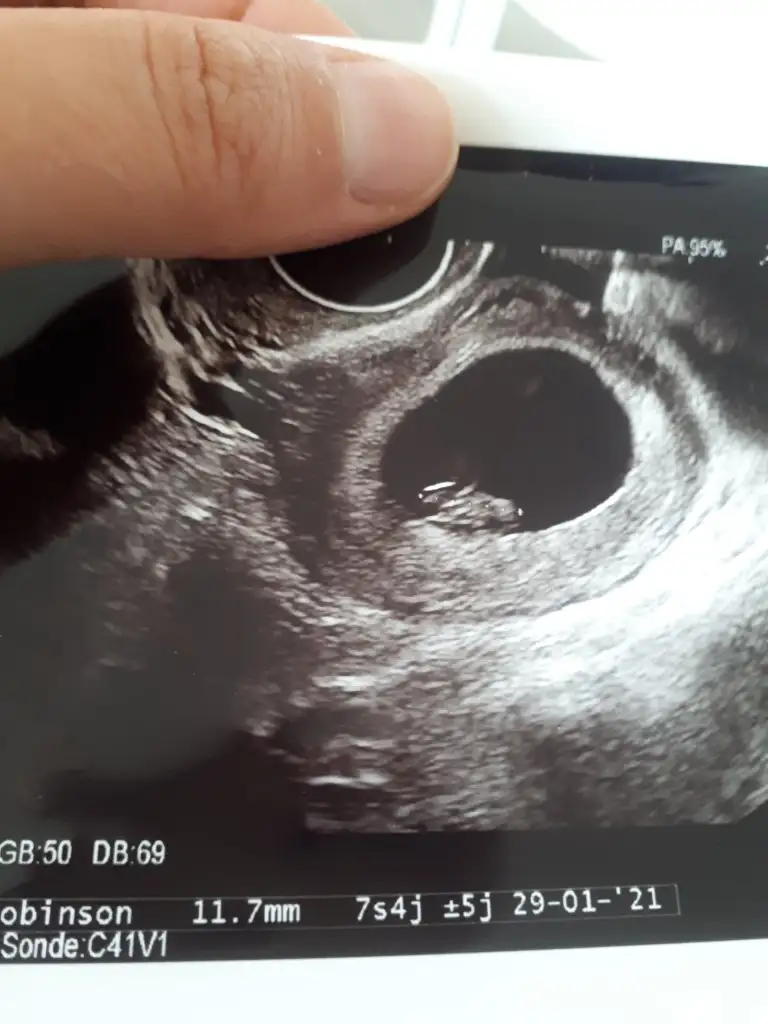

Hayırlı olsun canım inşallah sağlıkla al kucağınaTeyzeleri biz boleyiz sizin yokmu hic bebislerinizden fotolariniz galiba tek ben paylascamdogumumuz subatin 5 yaziyo burda qma ultrasyonda ocagin 29 cikmis bende yeni fark ettim